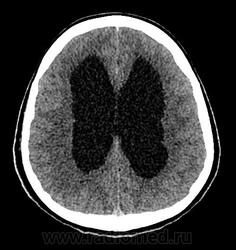

Девушка 30 лет. Поступила с диагнозом Эпилепсия. Неоднократные синкопы, начавшиеся после родов. Роды в начале марта, все благополучно. После родов, как-то так плохо все,шатает, голова болит. Через месяц обратилась в республиканскую больницу, выполнена кт- смешання гидроцефалия. Пролечили и выписали с диагнозом Дистония. Как-то так.

-признаки интравентрикулярной окклюзи выходных отверстий 4 желудочка, с резким расширением всех отдела желудочковой системы.

-резкое сужение охватвающей и большой цистерн

-выраженное расширение хиазмальной и предпонтийной цистерн

-межполушарная,латеральные щели и субарахноидальные пространства значительно уменьшены в объеме за счет увелиения желудочков и отека мозга

-истонены кости основания черепа,усилен рельеф внутренних костных пластин,углублено и расширено турецкое седло,опускание СЧЯ

-ствол и продолговатый мозг в дорсальном отделе уплощены,смещены вентрально

-в полости 4 желудочка объемное образование с учсатками кровоизлияния, с распространением каудально, признаки вклинения миндалин в БЗО,большая цистерна и САП кранио-вертебрального перехода не прослеживаются.